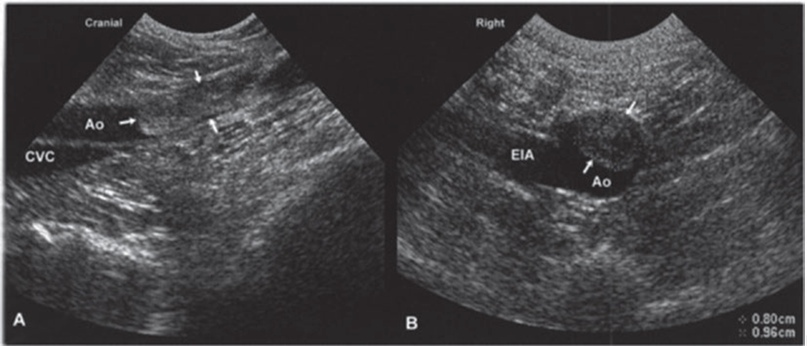

С помощью ультразвука можно визуализировать тромбы и эмболы. поражающие, помимо системы воротной вены, каудальную полую вену, аорту или подвздошные сосуды. При подозрении на тромбоэмболию в области таза необходимо исследовать все ветви сосудов, включая бедренные вены и артерии. Тромбоз в острой и хронической фазе будет визуализироваться по-разному. В начальной стадии тромб может быть гипоэхогенным, и его труднее идентифицировать при использовании стандартного В-режима. Четким диагностическим признаком для выявления острого тромбоза с помощью спектрального, цветного или энергетического доплера является отсутствие кровотока, а также отсутствие сжатия (применимо к дистальной части каудальной полой вены и периферическим венам). Через некоторое время можно визуализировать эхогенный очаг, заполняющий часть просвета сосуда, обычно прикрепленный к участку сосудистой стенки. Тромб может выглядеть однородным или неоднородным вследствие растворения кровяного сгустка и восстановления просвета сосуда. (Рис. 1) (Рис. 2).

Рис. 1. Тромбоэмболия аорты. Изображение каудальной части брюшной аорты (Ао) собаки со слабостью тазовых конечностей, полученноев продольной (А) и поперечной (В) проекциях. В просвете аорты визуализируется эхогенная трубчатая структура с относительно четкимиграницами, которая вызвала окклюзию большей части просвета сосуда и является эмболом (показан стрелками). У собаки был диагности-рован гиперадренокортицизм, который мог являться предрасполагающим фактором для формирования тромбов. CVC - каудальная полаявена; EIA - наружная подвздошная артерия